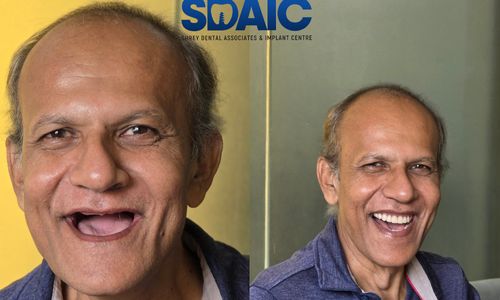

Before & After Results

See the difference expert care can make. Real treatments, real improvements, and real smiles restored with precision.